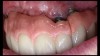

(14.) Photograph of fractured right lateral incisor taken with a smartphone and an EALS device during patient presentation for emergency treatment shown with accompanying radiograph.

Figure 14

(15.) Photograph of fractured right lateral incisor taken with a smartphone and an EALS device during patient presentation for emergency treatment shown with accompanying radiograph.

Figure 15